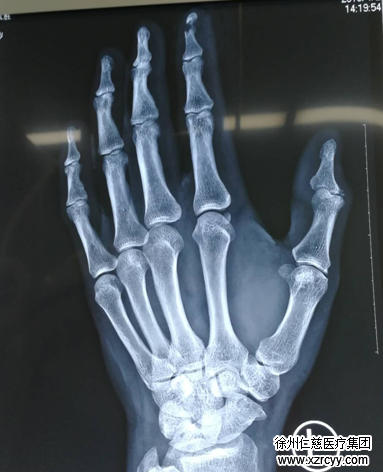

王加申又坐车来到必威官方首页官网betway。当天,手外科正好是董自强医生值班,他询问了王加申受伤的经过,又仔细检查了他的伤指,确定左手食指离断不全,需要做手术。

此时,距离王加申食指被咬断已经过去了6个小时,必须尽快对伤口进行抗感染对症治疗。术前准备快速进行,随即,王加申被推进手术室,董医生给他实施了左示指清创、骨折复位内固定、血管甲床皮肤撕脱修复术。

术中,先给患者清除污染失活组织,修整皮缘,左示指远节指骨骨折手法复位,在显微镜下吻合动脉,直至血管畅通。手术获得了成功。